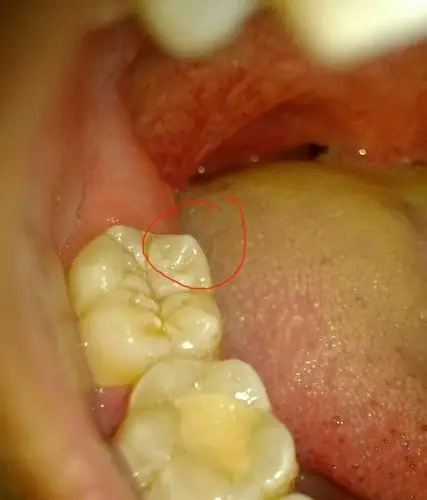

后牙龋坏完美修复一例